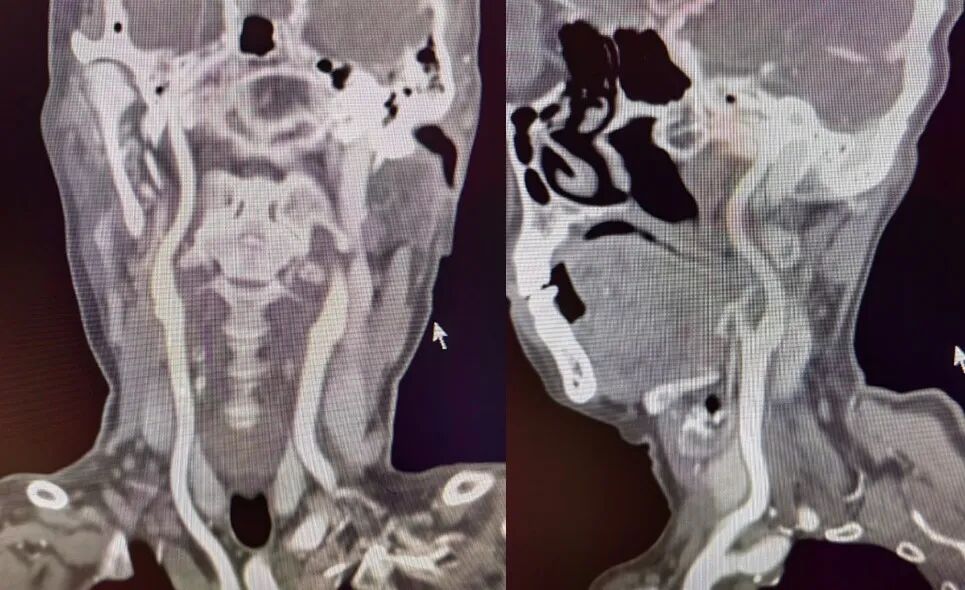

术后影像及随访

(术后8h CT)右侧放射冠区、右侧基底节区、右侧额叶多发急性梗死。

(术后7d CT)右侧放射冠区、右侧基底节区、右侧颞叶、额叶多发急性梗死。

(术后14d CTA)RMCA-M1支架植入术后改变。

导丝怎么扩【载药时代 球扩天下】NOVA DES®颅内药物洗脱支架在大脑中动脉重度狭窄的应用二例!_https://www.jmylbn.com_新闻资讯_第19张

导丝怎么扩【载药时代 球扩天下】NOVA DES®颅内药物洗脱支架在大脑中动脉重度狭窄的应用二例!_https://www.jmylbn.com_新闻资讯_第20张

NOVA DES®应用——2022年随访:

2022年6月23日:左上肢肌力2+级;左下肢肌力5-级;可流利行走;言语欠流利;神志清楚;NIHSS 5分;mRS 2分。